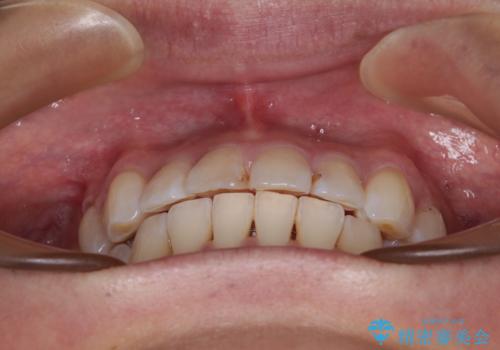

- 以前矯正治療を行ったものの、思い通りの仕上がりではなく、更には後戻りが気になってきたとのことで来院された患者様です。

上顎右側の第一小臼歯が動きにくい歯であり、以前矯正治療を行った際に傾斜した位置のまま終了したことと、それに伴い後戻りで歯列が波打っているようになっていることを大変気にしていらっしゃいました。